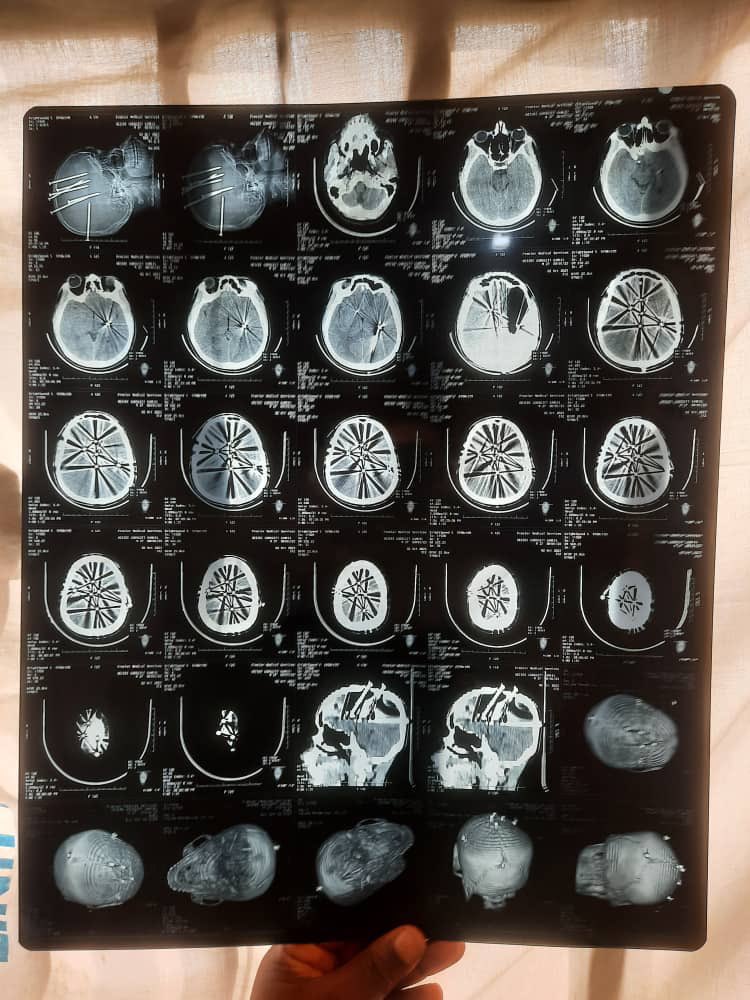

This is Dr Ubong Ekpene, a consultant Neurosurgeon in University of Uyo Teaching HospitalHe operated on a man who had 7 long nails hammered into his head . The operation was successful . The patient has been discharged without a single neurological deficit .